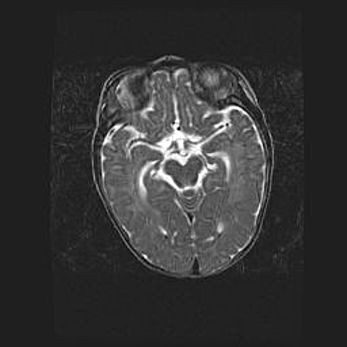

Лейкомаляция с кистозно-глиозной дегенерацией головного мозга.

Возраст: 2 месяца 25 дней

Вес: 6400 г

Окружность головы: 40 см

Срок гестации: 41 неделя

Лейкомаляцию относят к ишемически-гипоксическим повреждениям головного мозга, диагностируемым у новорожденных. При лейкомаляции в головном мозге обнаруживают очаги некроза, возникшие после тяжелой гипоксии и нарушения кровотока. В процессе морфогенеза очаги проходят три стадии: 1) развития некроза, 2) резорбции и 3) формирования глиозного рубца или кисты. Перивентрикулярная лейкомаляция (ПЛ) встречается примерно в 12% случаев среди новорожденных, обычно – у недоношенных детей, причем, частота ее зависит от массы, с которой младенец появился на свет. Наибольшее число малышей страдает лейкомаляцией, если масса при рождении 1500-2500 г.